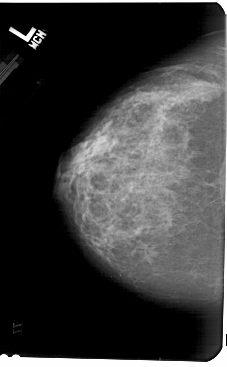

A_1569_1.LEFT_CC

LEFT_CC LINES 5491 PIXELS_PER_LINE 3391 BITS_PER_PIXEL 12 RESOLUTION 43.5 NON_OVERLAY